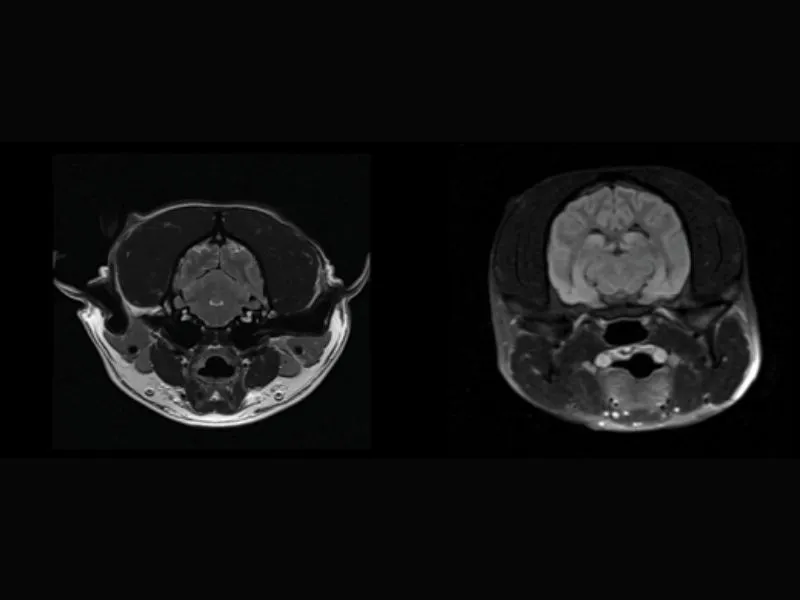

Supreme vet-mr – High resolution transverse T2W and FLAIR sequence of a large dog